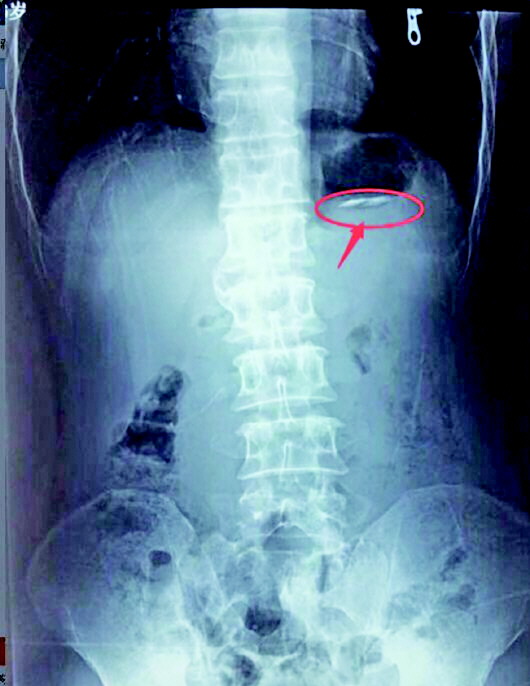

3日透视片中朱某胃里的刀片。(警方供图)

将手术取出钢针

3日上午10点,两人被送到城阳第三人民医院,各科医师对朱某、杜某进行了详细检查,并对两人拍摄胸腹透视片。据民警介绍,3日朱某落网当天拍过一次透视片,当时刀片的位置在朱某的胃部。据医生介绍,由于人体消化道内壁比较湿滑,吞食金属异物后,大部分异物会随着食物下行,经肠道排出体外,个别的异形物可能会卡在肠道折叠处。只要异物形状规则,长度小于六七厘米,人体自行排出的可能性很大,如果异物长期卡在消化道内,则必须手术取出,否则时间太久就会造成穿孔,危及生命。朱某第二次拍摄透视片时,医生未发现金属异物影像,初步诊断刀片已经排出体外。朱某将被警方送往看守所。